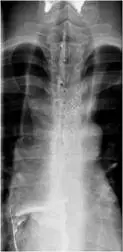

23歲男性,主訴吞嚥困難與經常性吸入性肺炎,上消化道鋇劑攝影檢查如下圖,最有可能的診斷為:

第一張為病患胸部正側位X光,顯示後縱膈可見持續性食道影增寬,並伴有水平的氣液平面,提示食道内容物長期滯留。第二張為上消化道鋇劑攝影(barium swallow)正位像,可見:

- 食道全長明顯擴張,内有鋇劑及殘餘食物碎屑停滯。

- 食道遠端在胃食道交界處呈現平滑、對稱的逐漸狹窄形態,形似鳥喙(bird’s beak)。

- 狹窄處下方鋇劑通過受阻,滯留時間長。

這些特徵與achalasia的典型鋇劑攝影表現相符:食道擴張加鳥喙狀狹窄,LES無法放鬆導致排空困難(radiologica.org)。